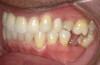

Fig 2. Candidates for hybrid teledentistry include patients with minor (Fig 2), moderate (Fig 3), and advanced crowding (Fig 4).

Fig 3. Candidates for hybrid teledentistry include patients with minor (Fig 2), moderate (Fig 3), and advanced crowding (Fig 4).

Figure 3

Fig 4. Candidates for hybrid teledentistry include patients with minor (Fig 2), moderate (Fig 3), and advanced crowding (Fig 4).

Figure 4

The author's practice established a partnership with one of these disruptive clear aligner companies that offer this hybrid approach as a means of attracting consumers who were largely educated about the model and were seeking optimal results. The practice provides the initial case assessment and takes records to help the partner determine if the patient is a candidate for clear aligner treatment (Figure 2 through Figure 4), then it is compensated for these services. From this point on, the hybrid model involves teledentistry backed by state licensed dentists and orthodontists with minimal disruption to the practice. This, in itself, is a revenue builder, as it enables minimum aligner treatment cost to be paid with no additional fees or membership dues.